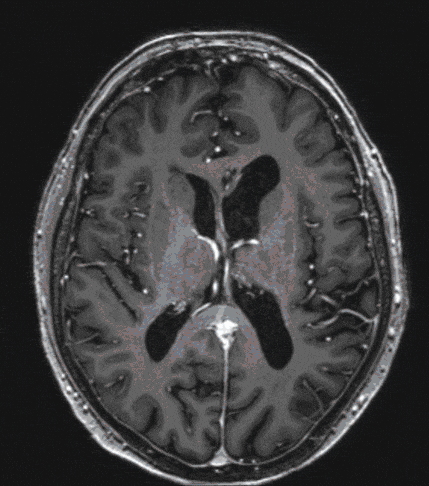

Pituitary Tumor

Pituitary tumors are usually benign tumors of the pituitary gland (hypophysis), which, if large enough, can lead primarily to visual disturbances and/or hormonal disturbances. Interdisciplinary treatment, both before and after surgery, is therefore crucial for the outcome.